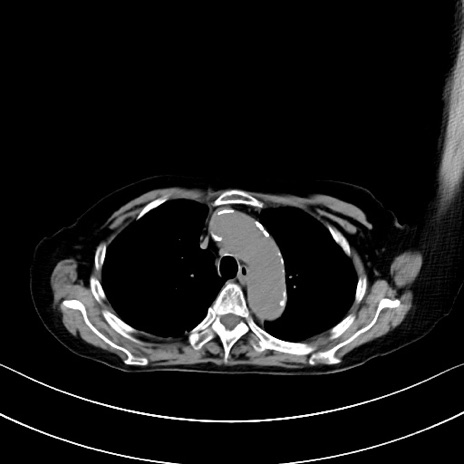

横断像

他院CT